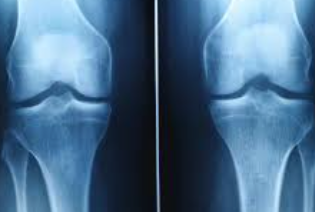

관절염과의 관계

무릎 연골 손상이 진행되면 결국 퇴행성 관절염으로 발전하게 됩니다. 초기 연골 손상 증상이 관절염의 전단계 증상으로 볼 수 있으며, 조기 발견과 치료가 관절염 예방에 매우 중요합니다.